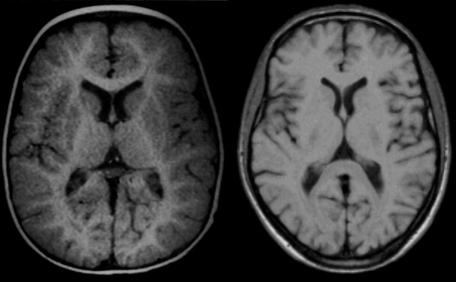

Figure 09-12:

Brain images of (a) an infant of 11 months, and (b) an adult at 0.5 T. The same pulse parameters were used (SE: TR = 500 ms, TE = 20 ms). Windowing is slightly dif­fe­rent.

Still, image contrast, in particular con­trast bet­ween gray and white matter is ob­vi­­ous­ly not the same because in the infant mye­li­na­tion has not reached the adult stage and both T1 and T2 of white matter are higher than T1 and T2 of gray matter.